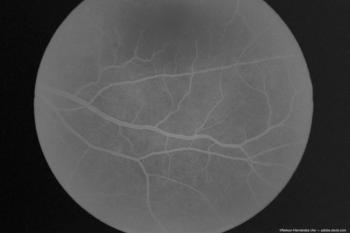

Researchers screened for outcomes such as the presence of retinal diseases including age-related macular degeneration and retinal vein occlusion

QUASAR is a global, double-masked, active-controlled phase 3 trial evaluating the efficacy and safety of EYLEA HD, compared to EYLEA, in patients with RVO, including those with central, branch and hemiretinal vein occlusions.

Researchers noted that patients with sickle cell disease had an increased risk of developing any retinal vascular occlusion.